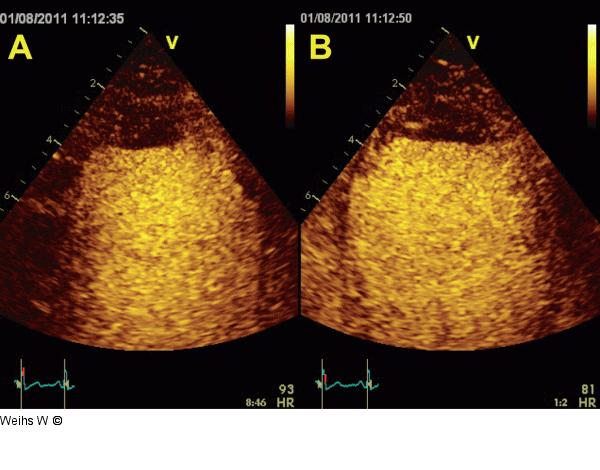

Abbildung 5a-b: Längsschnitt - Vierkammerblick Zoom der apikalen Segmente im apikalen Längsschnitt (a) und Vierkammerblick (b) während der Kontraststudie. In beiden Ebenenen stellt sich der apikale Thrombus dar. |

Zoom der apikalen Segmente im apikalen Längsschnitt (a) und Vierkammerblick (b) während der Kontraststudie. In beiden Ebenenen stellt sich der apikale Thrombus dar. |